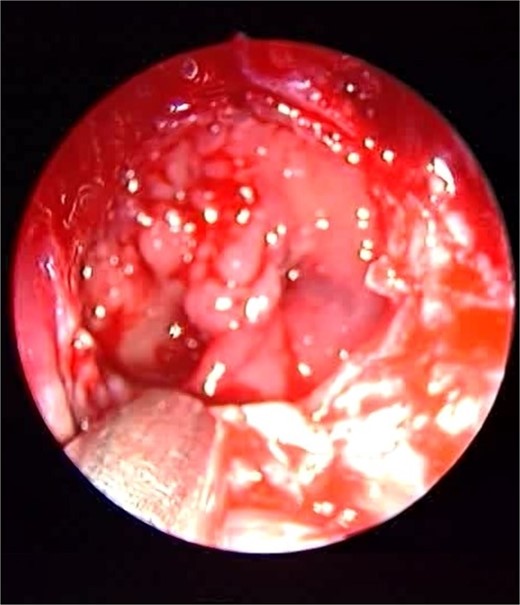

Patient presented to the emergency department with four days history of sever left side headache associated with nausea and vomiting, and nasal discharge with on\off nasal obstruction. Two days history of diplopia with lateral gaze of the left eye, with decrease the visual acuity. Ophthalmologic examination revealed left abducens nerve palsy. Other neurologic examinations were within normal. Endoscopic nasal examination revealed left multiple grade two nasal polyps occupying the middle meatus. Pre-operative brain computed tomography (CT) shows bilateral near total opacification and expansion of the paranasal sinuses and nasal cavity (Fig. 1). Additionally, there is evidence of invasion of the left cavernous sinus with encasement of cavernous segment of left internal carotid artery (ICA). Furthermore, pituitary gland and optic chiasm displaced superiorly. Magnetic resonance imaging revealed that the sphenoid sinus is expanded and bulging superiorly into the pituitary fossa causing displacement of pituitary gland and stalk without mass effect upon the optic chiasm (Fig. 2). It extends laterally causing effacement of the cavernous sinus and left Meckel’s cave. No evidence of intracranial extension. The patient underwent functional endoscopic sinus surgery with computer-assisted navigation system. Intraoperatively, sphenoid sinus was full of fungal mud and mucin (Fig. 3). The polyps were removed completely from the nasal cavities, fungal mud, and mucin were removed from the sinuses (Figs 4 and 5). Patient had dramatic improvement after surgery, the rhinosinusitis symptoms are resolved, the diplopia has been improved, and the paranasal sinuses were clear. The patient was discharged with topical corticosteroid and saline irrigations.

Endoscopic intraoperative image of the sphenoid sinus post removal of the fungal mud and mucin from the lateral wall of the sphenoid sinus.